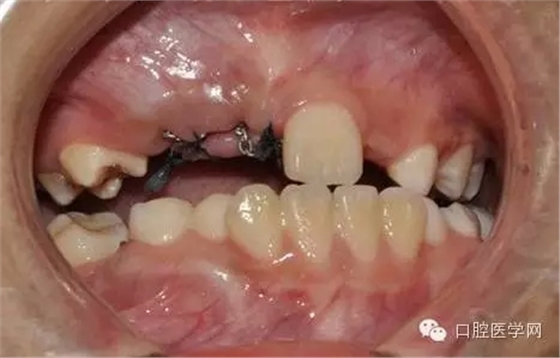

切開:

去除部分礙事牙囊,充分暴漏牙冠便于粘結(jié)正畸附件,并用大量腎上腺素壓迫止血。

酸蝕后

光固化型正畸粘結(jié)劑粘結(jié)鏈?zhǔn)綘恳b置

鏈狀正畸牽引裝置粘固后的口內(nèi)情況